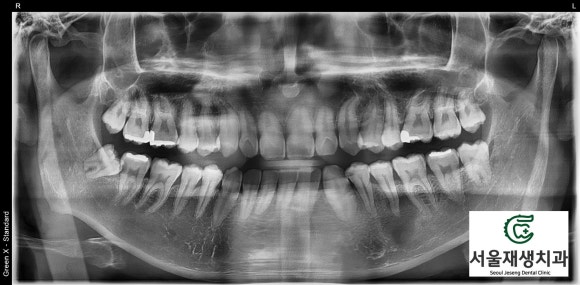

X-ray를 통해 뿌리 끝 염증을 관찰!

![[치외치신경치료] 뿌리 끝 염증이 커서 발치해야된대요! 치아 머리에 볼~록! 알고보면 무서운 작은 혹 (서울재생치과) 관련 이미지 10](https://pub-9f2bb3498faf4d1d8714b41df24753e3.r2.dev/content/clinics/archive/nqmm0udu86/naver_blog/honeybeevuvu/assets/by_hash/10f59e16229876a515c5aab5294ce63cd502d1050a2410575aae82bc50a5cedc.jpg)

치과 엑스레이 검사의 가장 기본이 되는

파노라마 엑스레이입니다.

조금만 더 확대해볼까요?

![[치외치신경치료] 뿌리 끝 염증이 커서 발치해야된대요! 치아 머리에 볼~록! 알고보면 무서운 작은 혹 (서울재생치과) 관련 이미지 11](https://pub-9f2bb3498faf4d1d8714b41df24753e3.r2.dev/content/clinics/archive/nqmm0udu86/naver_blog/honeybeevuvu/assets/by_hash/7f5faaa71c7684e360752df8620c74f0f6416559dc3e7d4c32e5f10f79f44df5.jpg)

아하...

아래 어금니 앞에 있는

작은 어금니의 뿌리 주위로

심상치 않은 기운이 느껴집니다.

![[치외치신경치료] 뿌리 끝 염증이 커서 발치해야된대요! 치아 머리에 볼~록! 알고보면 무서운 작은 혹 (서울재생치과) 관련 이미지 12](https://pub-9f2bb3498faf4d1d8714b41df24753e3.r2.dev/content/clinics/archive/nqmm0udu86/naver_blog/honeybeevuvu/assets/by_hash/d9165ef2b2fa57c1c71cddfbb8a791e8a8dfa368a13539ce3b5028aab989a652.jpg)

뼈를 광범위하게 녹이고 있는

뿌리 끝 염증!!

치아 신경은 이미 감염되었고,

감염 부산물들이 뿌리 끝에 나있는

작은 구멍을 통해 배출되다보니

뼈까지 손상을 시키게 된 것이죠...